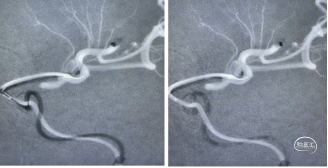

造影右侧大脑前动脉缺如(未发育),左侧大脑前A2段闭塞。

1、微导丝越过闭塞处到达A3段。下图1

2、5F 125中间导管辅助高到位下图2。

3、手推造影明确血栓位置下图3。

4、微导管到达A4段下图4。

5、3*20取栓支架到位回撤微导管,多点显影标记,清晰可见支架打开良好下图5。

造影显示血管再通。